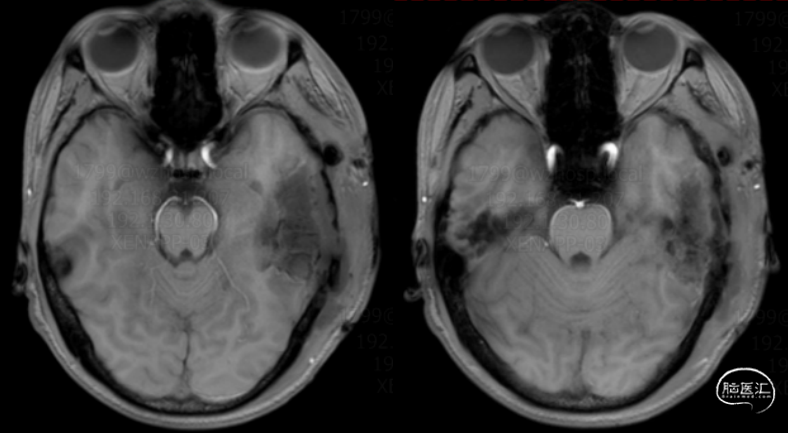

术前头颅MRI:左颅内占位术后,左颞叶混杂信号团块。

诊断:左侧颞叶肿瘤术后复发,继发性癫痫。